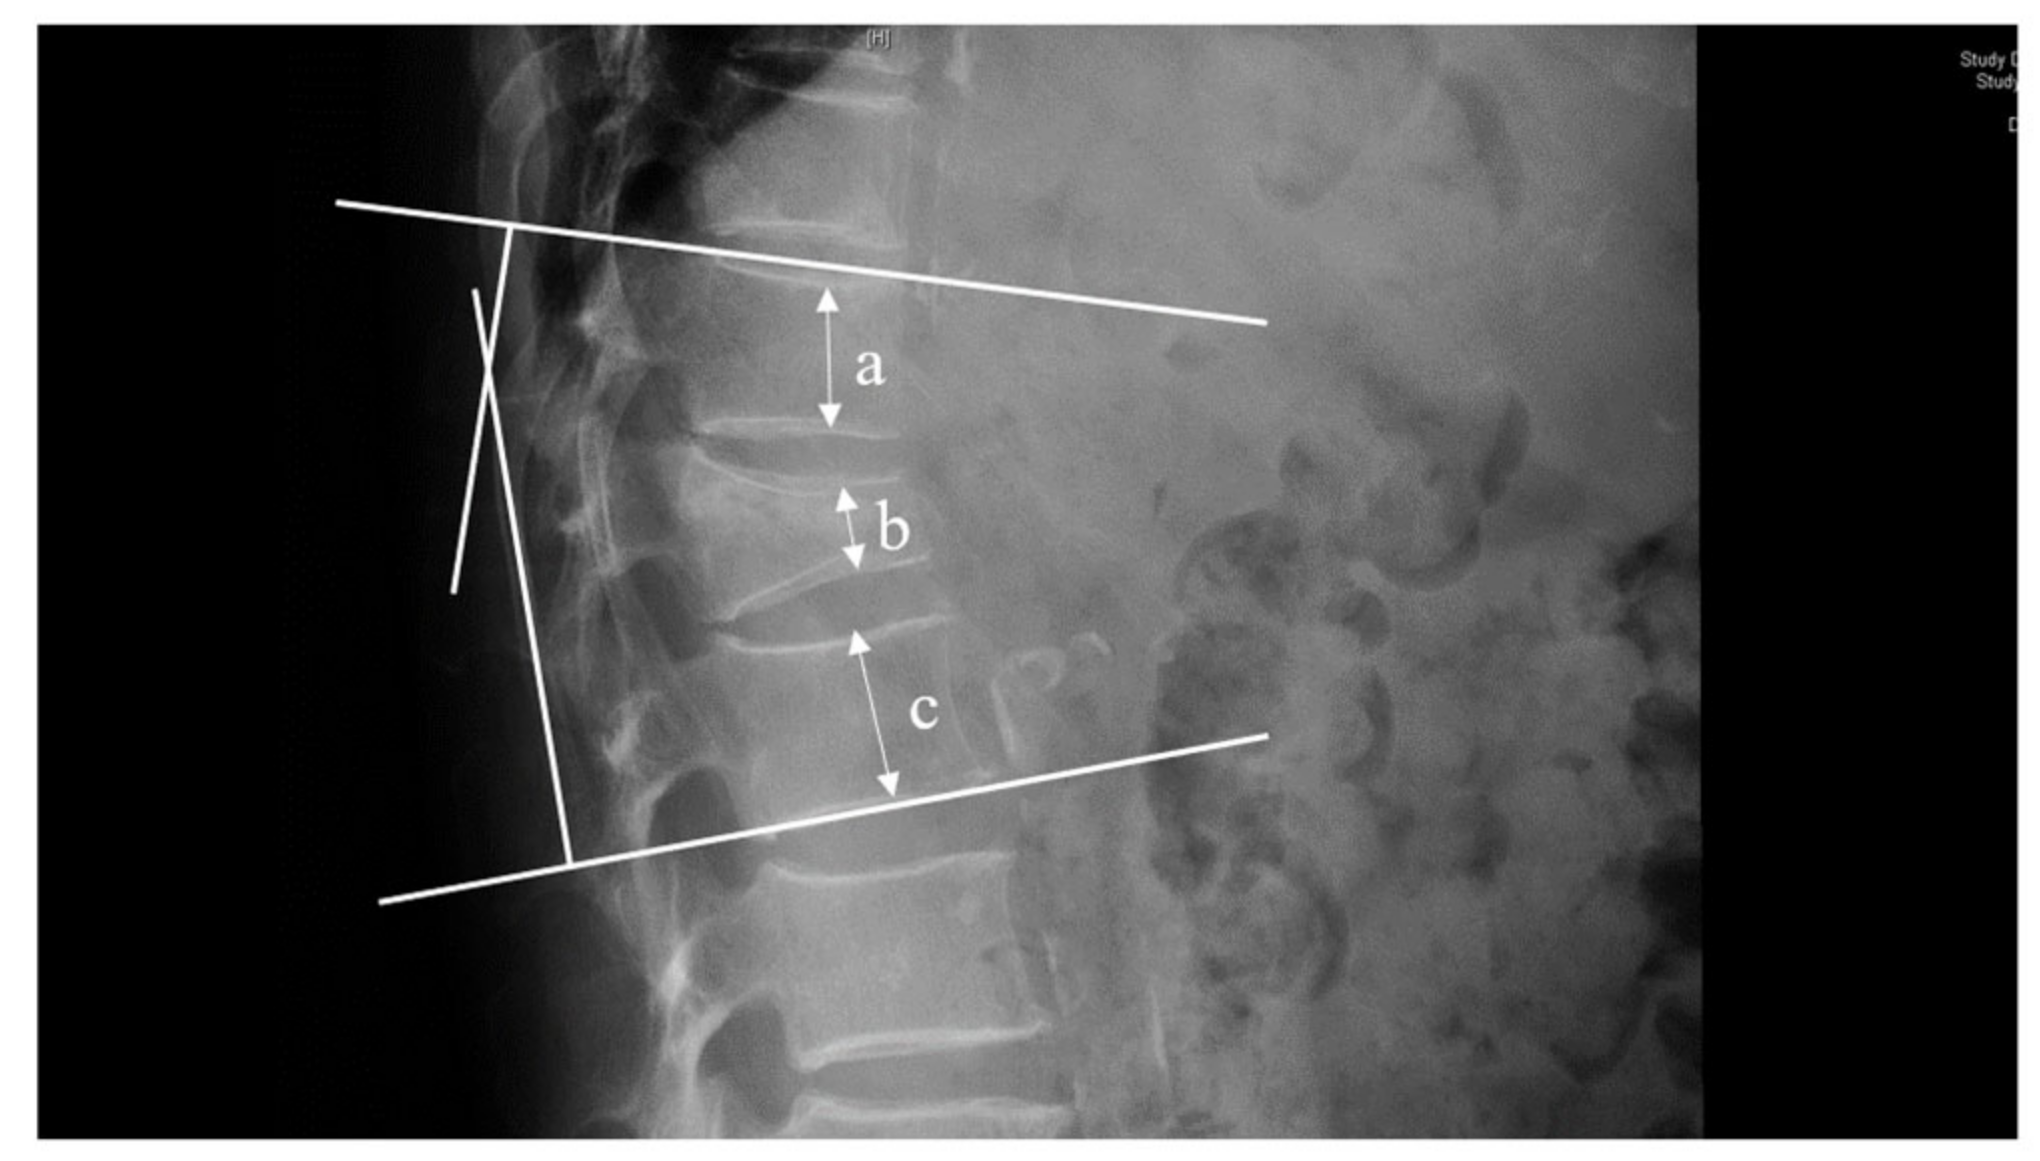

| Kyphotic angle | |||||||

| Preoperative (°) | 22.06 ± 5.87 | 21.71 ± 6.20 | 21.10 ± 3.34 | 0.313 | 0.203 | 0.519 | 0.869 |

| Postoperative (°) | 20.75 ± 7.31 | 18.39 ± 5.19 | 18.31 ± 5.83 | 0.157 | 0.076 | 0.953 | 0.054 |

| Restoration of kyphotic angle (%) | 17.21 ± 11.63 | 20.79 ± 14.34 | 23.38 ± 17.71 | 0.207 | 0.113 | 0.393 | 0.339 |

| At the last follow-up (°) | 21.51 ± 6.19 | 18.72 ± 5.38 | 18.87 ± 5.75 | 0.045 | 0.037 | 0.879 | 0.046 |